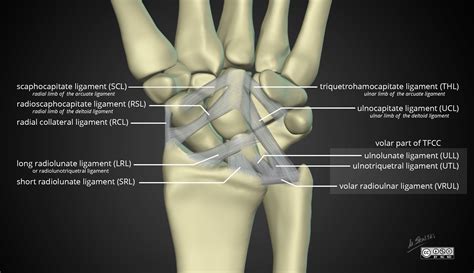

Understanding the Anatomy of the Wrist

The wrist is not a single joint but a complex assembly of multiple joints that allow for a wide range of motion. It includes the distal radius and ulna, the carpal bones arranged in two rows, and the base of the metacarpals. Supporting these bones is a sophisticated network of ligaments and tendons that stabilize the structure while facilitating movement. Due to this complexity, an MRI wrist joint scan provides the detailed, cross-sectional views necessary to evaluate these structures individually.

| Ligaments | Stabilize bones | Tears, sprains, or attenuation |